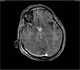

Enhancing sellar lesion